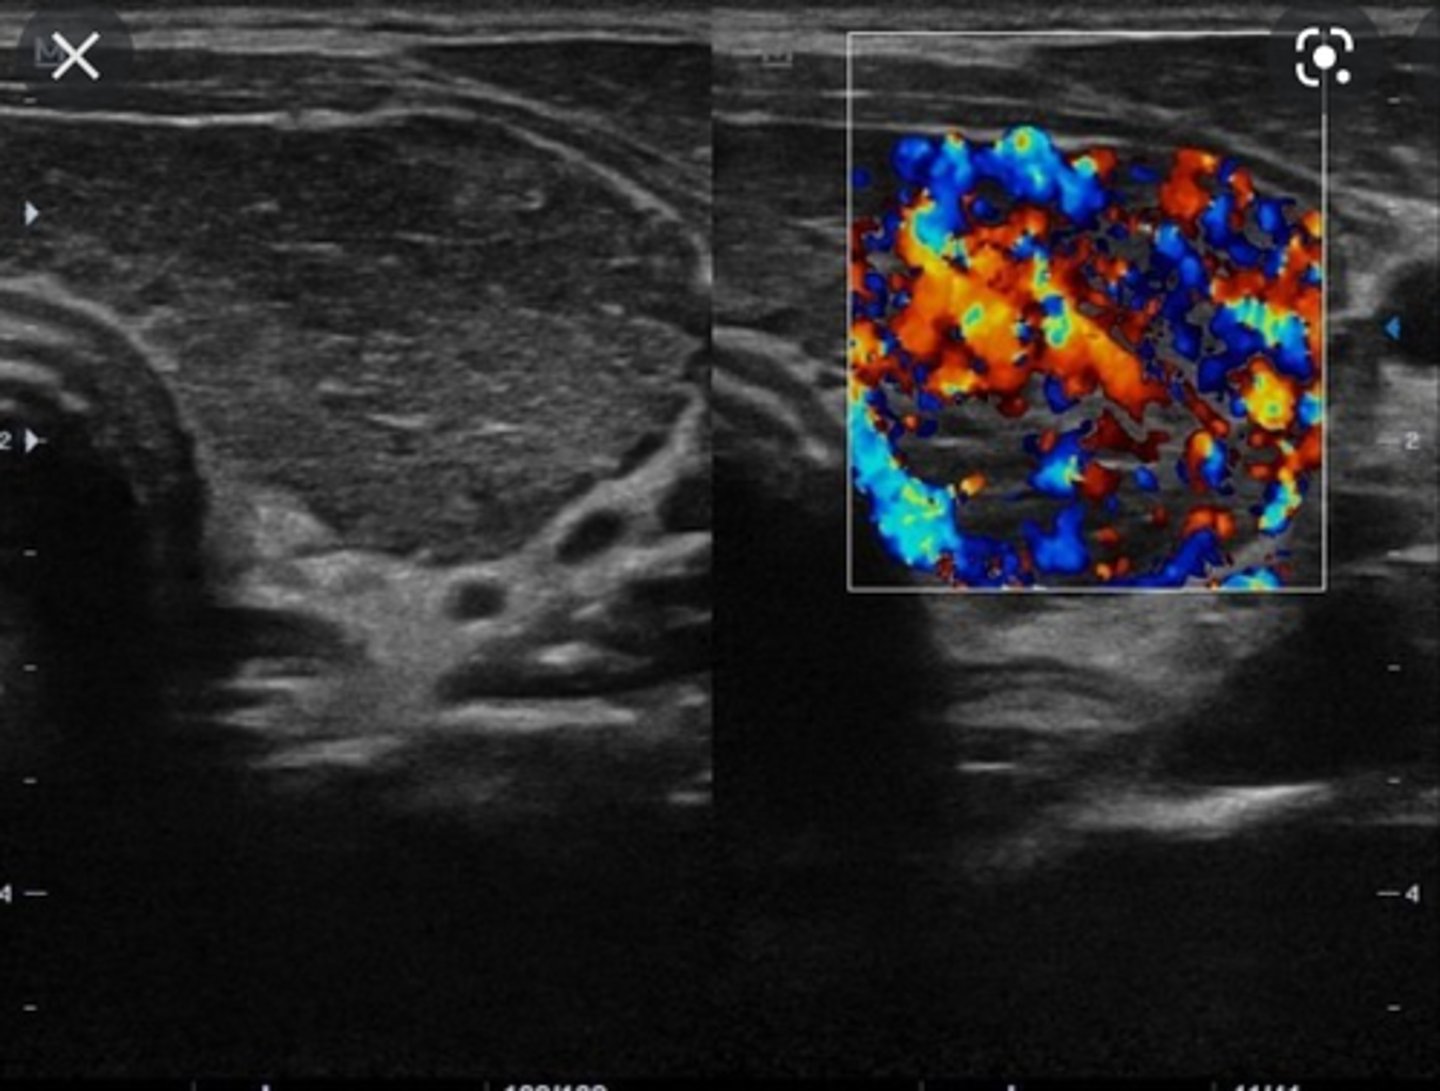

Benign Thyroid Neoplasms - Hashimoto disease:

Etiology

-Chronic ____ ____ disease

Clinical findings

-Often _____

-_____thyroidism

-Leukocytosis

-Sore _____

-_____

Sonographic findings

-_____ _____echoic thyroid glands

-_____vascular parenchyma

-Chronic lymphatic inflammatory disease

-Often painless

-Hypothyroidism

-Sore throat

-Fever

-Enlarged hypoechoic thyroid glands

-Hypervascular parenchyma